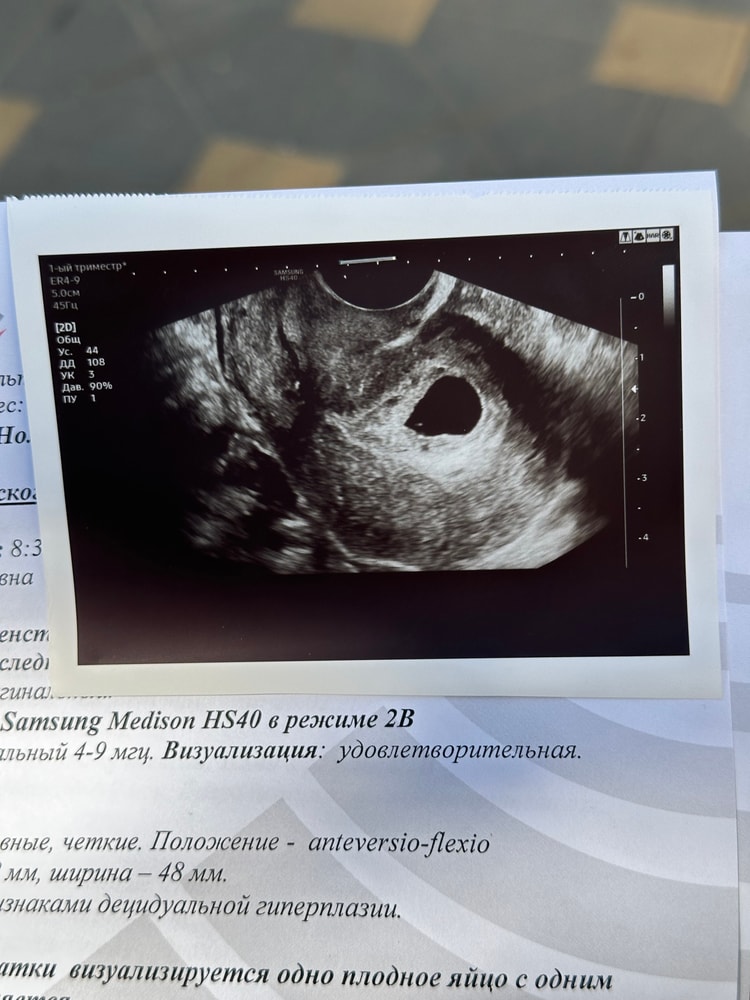

Подождите, конечно. Если интересно, то вот моё УЗИ, при пя в 21 мм не нашли жм и эмбрион, уже готовилась морально к чистке, и через 3 дня, всё появилось. Ниже фотки с узи загружу.